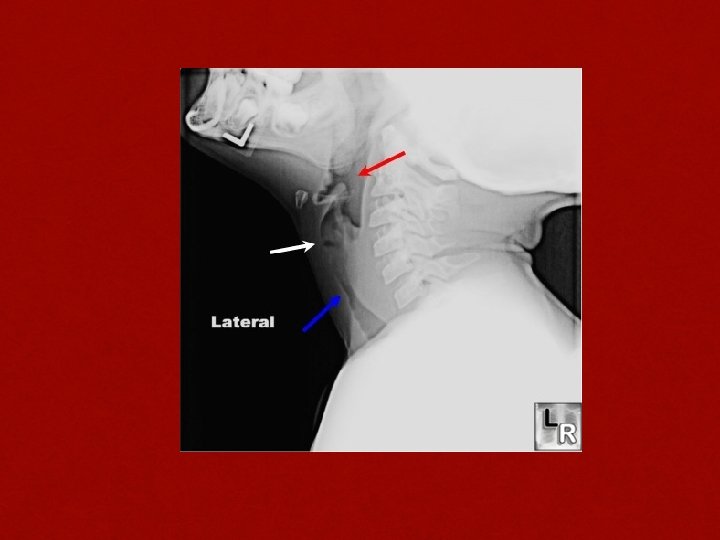

Lateral soft tissue X ray of neck THUMB SIGN